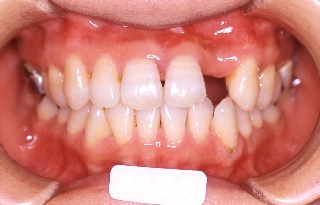

初診時年齢52歳。上顎前歯部欠損部インプラント治療前の咬合改善目的に来院。

当院にて前歯部の被蓋の改善を行った。

治療前 治療後

正面 正面 正面